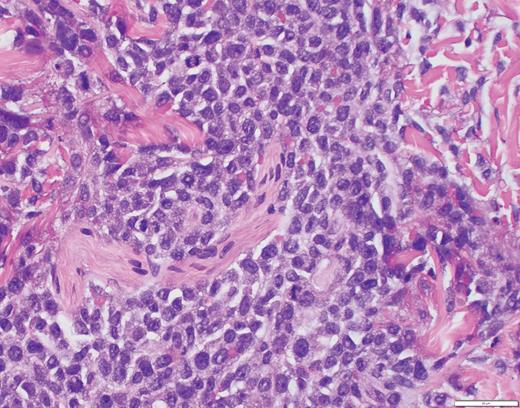

Biopsy of the affected tissue with histopathology and immunohistochemical stains is essential to making the correct diagnosis. The five most common phenotypic markers include CD4, CD56, CD123, CD303, and TCL1, though CD4-negative and CD56-negative cases have been reported.9,16 CD303, TCF4, and TCL1 are specific to pDCs and can help to solidify the diagnosis.15,16,18 BPDCN is negative for other lineage-specific markers such as MPO, T cells (CD3), B cells (CD20 and CD79a), and monocytes (CD11c, CD163, lysozyme).15,16,18 The plaque biopsied in Case 2 demonstrated a dense atypical infiltrate composed of medium-size cells with irregular nuclear contours, fine chromatin, and scant cytoplasm, resembling undifferentiated blast cells with frequent mitoses diffusely involving the dermis (Figure 5). The infiltrate was negative for B-cell and T-cell lineage markers and MPO while positive for CD4, CD123, and TCL1A, supporting a diagnosis of BPDCN.

Case 2 histopathology showing dense atypical infiltrate composed of medium-size cells with irregular nuclear contours, fine chromatin, and scant cytoplasm, resembling undifferentiated blast cells with frequent mitoses and scattered admixed foamy macrophages, some with hemosiderin diffusely involving the dermis. (A) Hematoxylin and eosin stain (2×); (B) hematoxylin and eosin stain (40×).